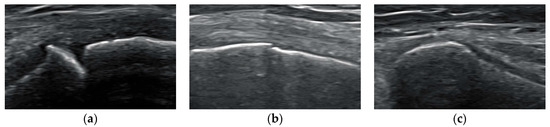

| Definition of Stages 1–3 | |

|---|---|

| Stage 1 | The growth plate is open and there is a large gap (2–3 mm) between epiphysis and metaphysis. From the outer cortex into the physis, there is a right-angle step-off (metaphyseal zone of calcification) (Figure 1a). |

| Stage 2 | The growth plate has a small diameter. There is only a shallow notch between epiphysis and metaphysis (Figure 1b). |

| Stage 3 | The growth plate is closed. No gap can be seen between epiphysis and metaphysis (Figure 1c). |